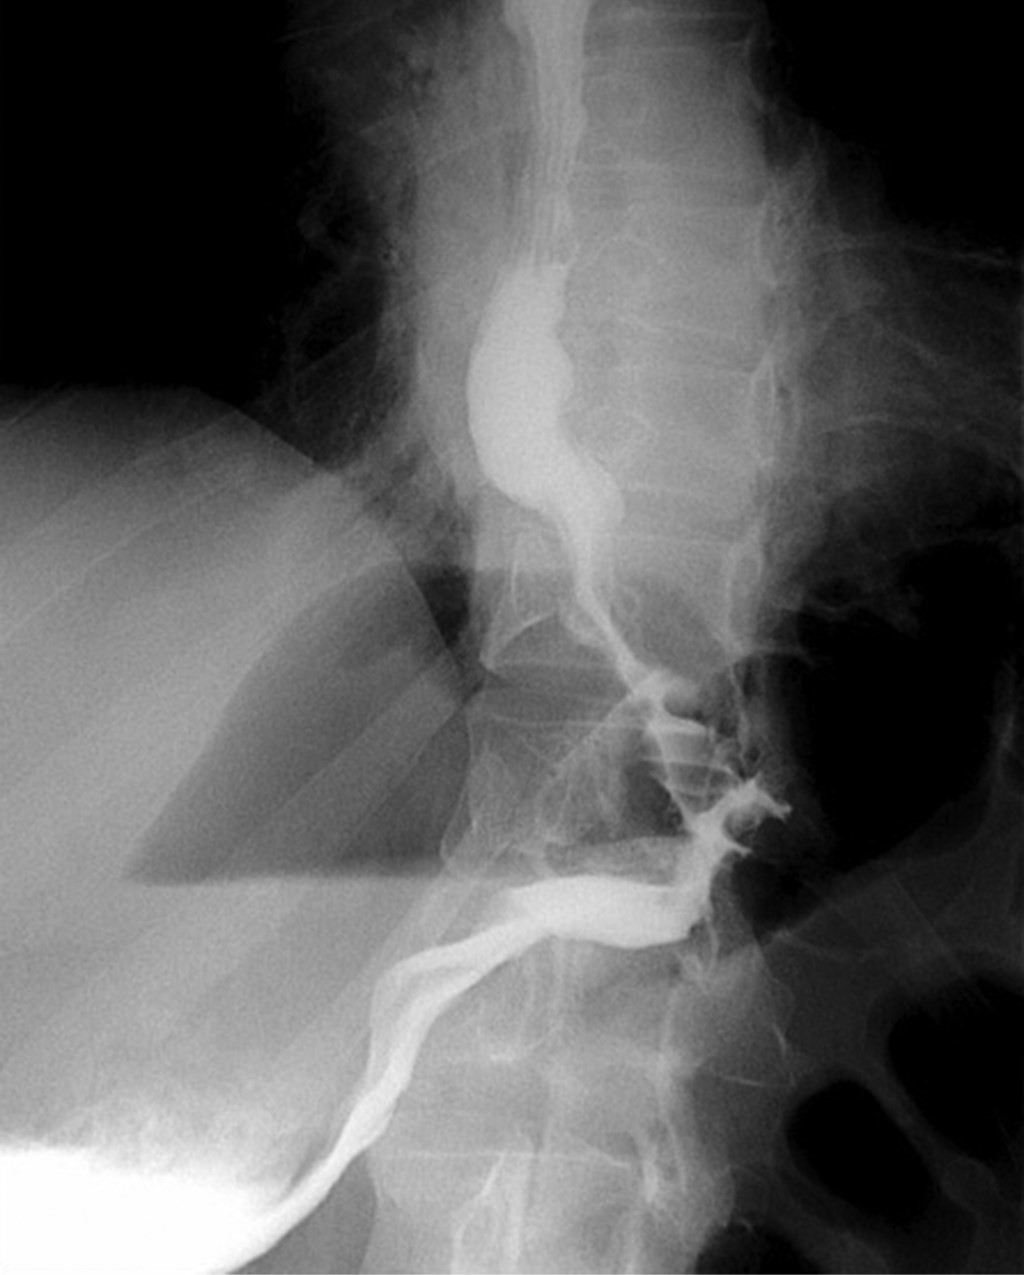

El paciente fue hospitalizado y se le efectuó tomografía toracoabdominal, que reportó al estómago con engrosamiento de sus pliegues y signo de remolino hacia la región del píloro, confirmando la sospecha diagnóstica (Figura 2), por lo que se optó por la resolución quirúrgica urgente mediante laparoscopía, detorsión gástrica y gastropexia (Figuras 3 y 4). La evolución fue satisfactoria; un esofagograma con medio hidrosoluble de control posquirúrgico confirmó la ausencia de complicaciones a las 12 horas de la cirugía y el paciente pudo egresar para seguimiento por consulta externa tras cuatro días de estancia hospitalaria (Figura 5).

Por otra parte, los estudios contrastados ayudan a delimitar mejor la anatomía y aportan cierto beneficio para la planeación quirúrgica. De acuerdo con un estudio publicado por Teague y su equipo, los estudios contrastados confirmaron el diagnóstico en la mayoría de los pacientes de su serie de casos (14 de los 25 pacientes considerados).3,14

Albas y equipo describieron cuatro hallazgos que predicen un vólvulo gástrico por radiología con buena sensibilidad: a) niveles hidroaéreos por encima del diafragma, b) escaso aire distal en el intestino, c) inversión de la posición de la curvatura mayor del estómago y d) píloro apuntando hacia abajo.13

Figura 5